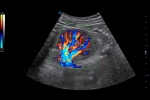

- Category: Color Doppler

CHI

Fewer contrast agents needed, SIUI’s Contrast Harmonic Imaging delivers uniformed image quality and longer duration. Common probes are enough to obtain strong penetration with CHI.